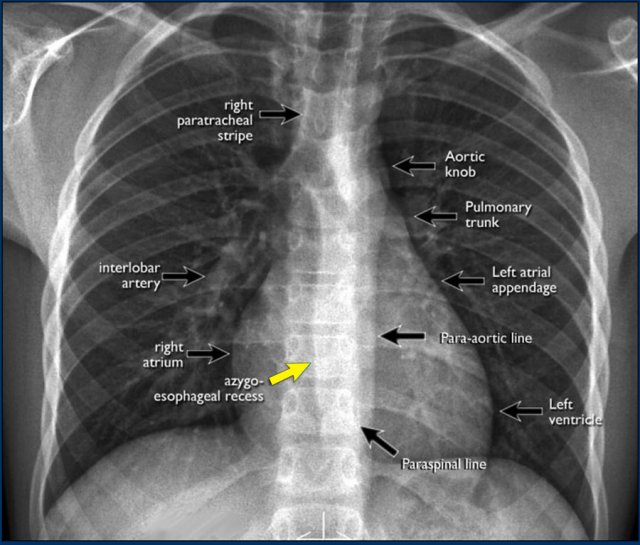

PA view

On the PA chest radiograph, careful evaluation of all interfaces between the lungs and adjacent structures—such as the diaphragm, heart, and mediastinum—is essential.

At these interfaces, lung–soft tissue boundaries form visible:

• Lines or stripes (e.g., the right paratracheal stripe)

• Silhouettes (e.g., the aortic knob or left ventricular contour)

These lines and silhouettes serve as anatomical landmarks and help localize pathology. When these contours are displaced or obscured with loss of the normal silhouette, the silhouette sign is present—a key diagnostic feature .

• The paraspinal line may be displaced by a paravertebral abscess, vertebral fracture with hemorrhage, or extravertebral extension of a neoplasm.

• Widening of the right paratracheal stripe (>2–3 mm) may indicate lymphadenopathy, pleural thickening, hemorrhage, fluid overload, or congestive heart failure.

• Displacement of the para-aortic line can be associated with aortic elongation, aneurysm, dissection, or rupture.

A key mediastinal–pulmonary interface to assess is the azygoesophageal recess (yellow arrow).

Azygo-esophageal recess

The azygoesophageal recess is located below the level of the azygos vein arch.

In this region, the medial aspect of the right lower lobe abuts the mediastinum between the heart anteriorly and the vertebral column posteriorly.

On its left, it is bordered by the esophagus.

Deviation of the azygoesophageal line may result from:

• Hiatal hernia

• Esophageal pathology

• Left atrial enlargement

• Subcarinal lymphadenopathy

• Bronchogenic cyst